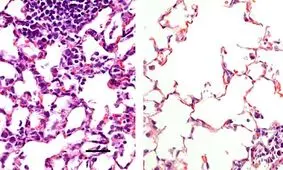

دانشمندان دانشکده پزشکی